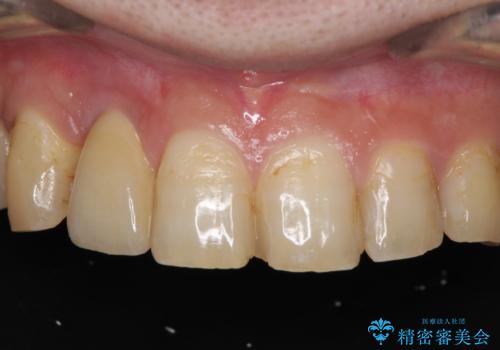

折れてしまった前歯 インプラントによる補綴治療